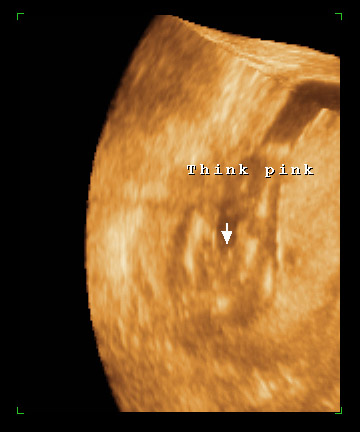

so we went to a place called Prenatal Treasures, which is an ultrasound place) to find out what we where having because i couldn't stand it anymore!

and they said...

IT'S A GIRL!

they were pretty positive that's what it was but she said we could come back in two weeks for a free ultrasound to be sure, but now we don't know!

here is pictures of our little munckin at 16 weeks!